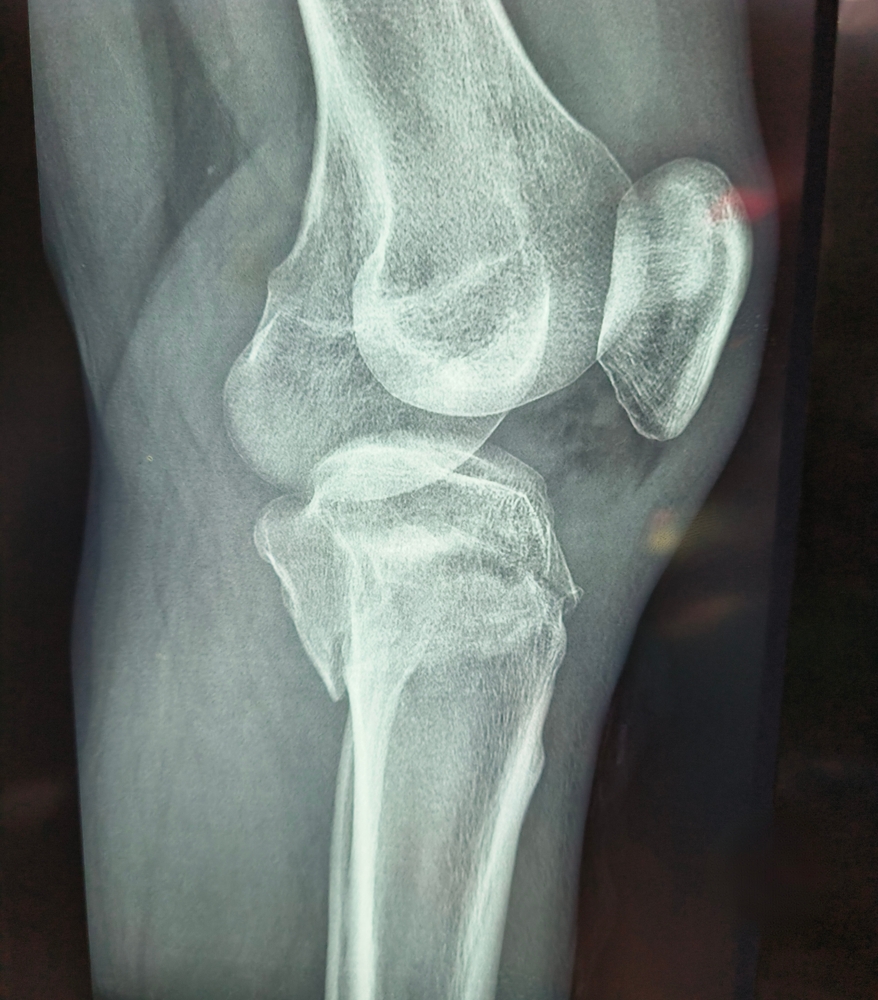

Kreipiantis į medikus, diagnozei patvirtinti gali būti atliekami rentgeno, kompiuterinės tomografijos ar magnetinio rezonanso tyrimai.

Lūžių klasifikacija pagal Schatzker

Norint tiksliai įvertinti lūžio tipą ir parinkti gydymą, naudojama šešių tipų sistema:

- I tipas – pleišto formos, nedaug praspaudęs (<4 mm) lūžis

- II tipas – I tipo lūžį lydi kaulo įduba

- III tipas – šoninės blauzdikaulio plokštelės įduba (IIIa – šoninė, IIIb – centrinė)

- IV tipas – vidinės blauzdikaulio pusės lūžis su įtrūkiu ar įduba

- V tipas – pleišto formos abiejų kelio dalių (vidinės ir išorinės) lūžis

- VI tipas – skersinis lūžis, atskiriantis kaulo vidurinę dalį nuo siauresnės

Kuo aukštesnis klasifikacijos tipas, tuo sunkesnis lūžis ir sudėtingesnis gydymas.